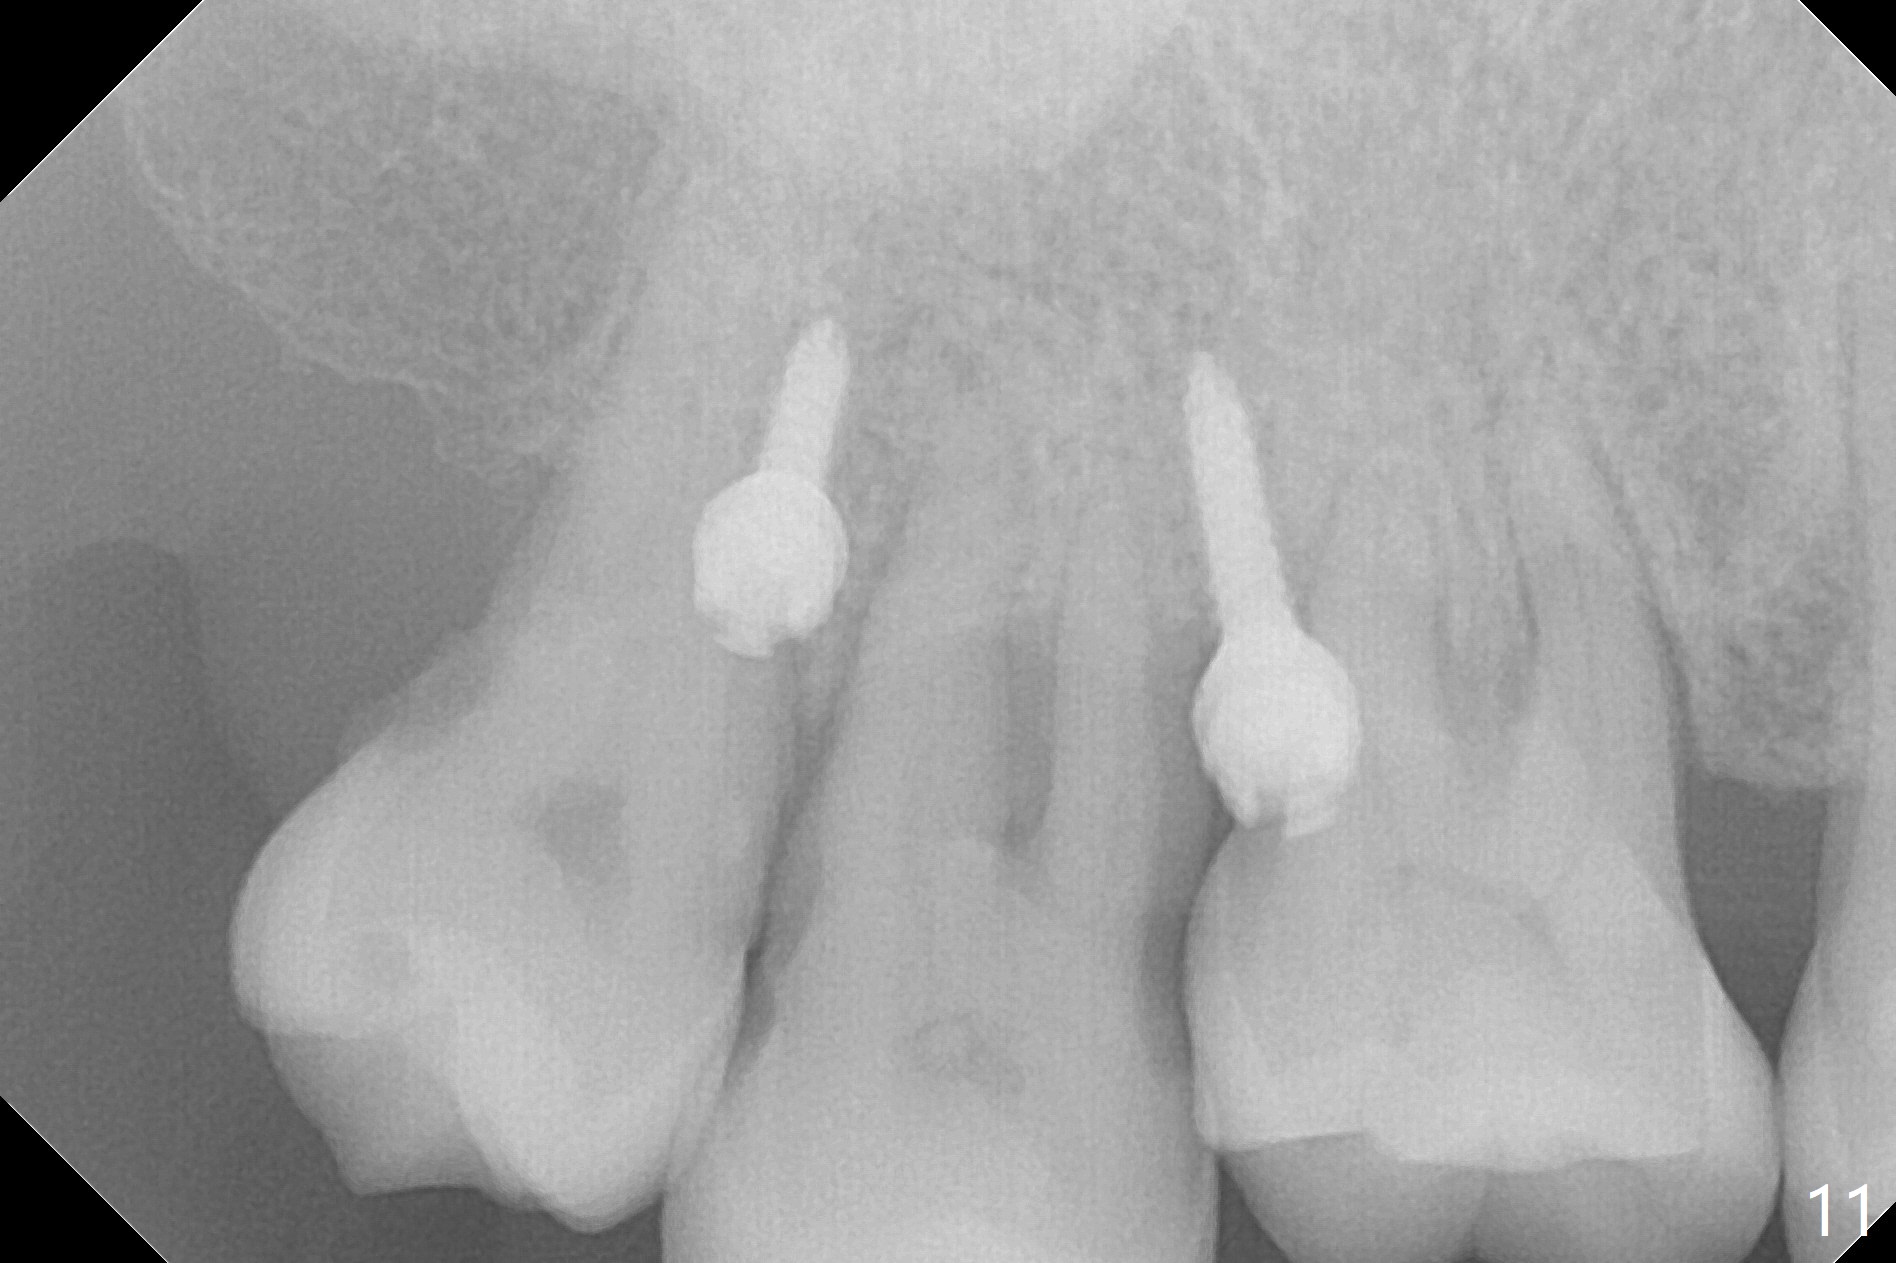

The buccal implant becomes loose in 2-3 months. When the wound heals (Fig.9 <), a 1.6x`10 mm implant is placed with the help of PAs for trajectory (Fig.10,11) and in the nonkeratinized gingiva (higher, the crestal bone may have been traumatized by previous implant placement, Fig.12). Two months later, the tooth #2 is partially intruded (Fig.13). A provisional (Fig.14 P) is fabricated in the osteointegrated implant at #31 with supraocclusion so that the remaining dentition has no occlusal contact (*). The periodontally compromised tooth #2 becomes in buccoversion in 2 months. The provisional is removed, while a lingual button is placed in the buccal surface of the tooth #2 (Fig.15). With power chain attached to the lingual mini-implant, the tooth #2 is lingualized in 2 months. The provisional and the implants are reused for final intrusion (Fig.16). The treatment is nearly 11 months. The buccal implant, although placed in the movable mucosa, remains stable and healthy (Fig.17). The tooth #1, as a guiding plane (to prevent #2 from distalization during intrusion), is not extracted after intrusion is completed.